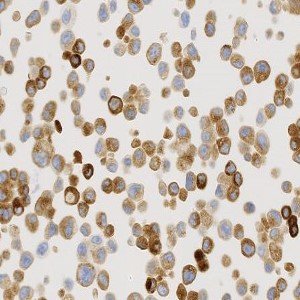

Positive cell line core, with strong cytoplasmic granular staining pattern.

The Staining Pattern of ROS1 Translocation will have a strong cytoplasmic granular staining observed in the positive cell line core. No cytoplasmic, granular staining pattern observed in the negative cell line core. Stained on the Automated Leica BOND stainer (Cell Signalling, D4D6, #3287).